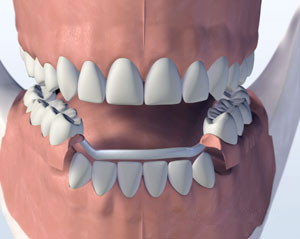

Full Arch Dental Implants

More and more Philadelphia residents are choosing full-arch dental implants to replace entire rows of teeth. This method uses several implants to support a one-piece set of replacement teeth.

After placing four to six implants, you’ll wear temporary dentures during healing. Once the implants fuse with the jawbone, the permanent teeth are attached with metal screws called abutments.